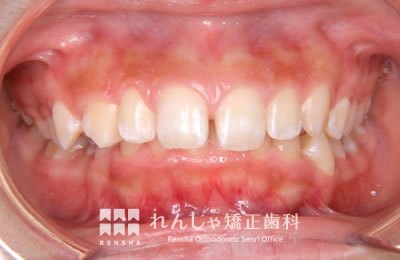

中高生

永久歯列はほぼ完成してしますが、歯列を側方だけでなく後方へも拡大し、埋まっていた右上奥歯を引っ張り出しています。

治療中

→

治療後

| 主訴 | 埋まったままでてこない歯がある |

|---|---|

| 診断名 | Angle Class II 小臼歯の埋伏と叢生を伴う上顎前突 |

| 初診時年齢 | 13歳5か月 |

| 装置名 | マルチブラケット装置 |

| 抜歯非抜歯 | 非抜歯 |

| 治療期間 | 2年3か月 |

| 費用の目安 | 約82万円+消費税(検査料金、都度の処置費用等も合わせた総額) |

| リスク副作用 | 歯の移動に伴う軽微な歯根吸収、歯槽骨吸収、歯肉退縮(本症例では軽度の歯根吸収を認めた)、矯正器具装着中のカリエスリスク増大(本症例ではカリエス発生無し) |